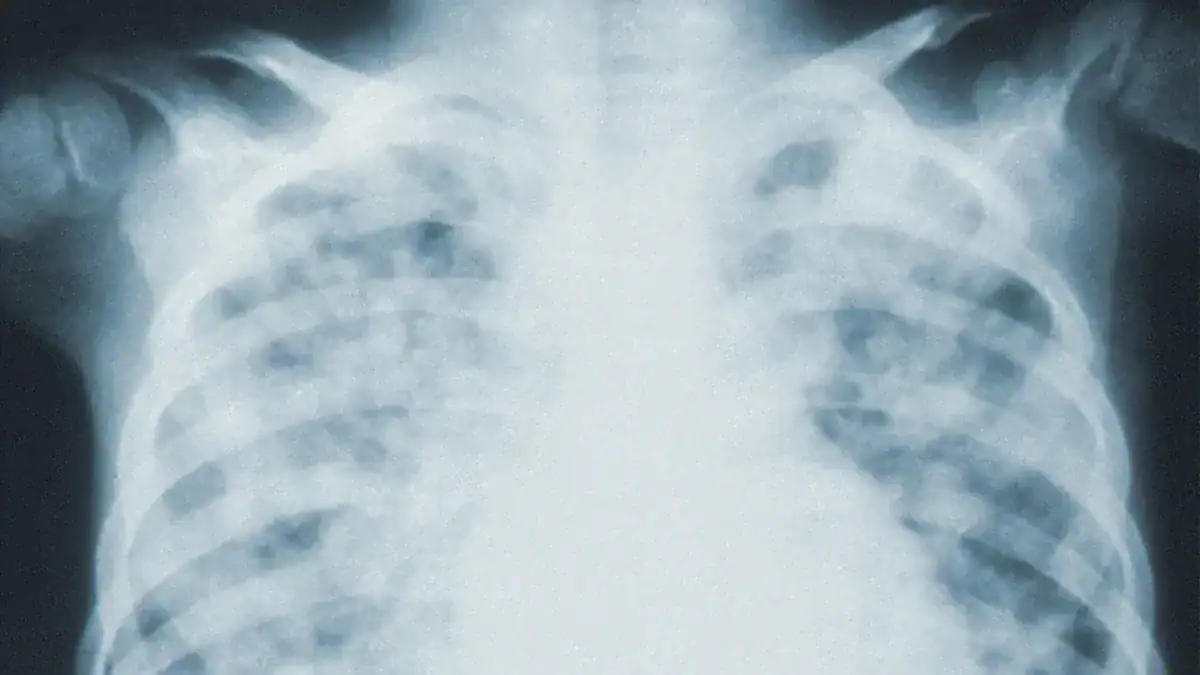

Imaging Tests

Imaging tests are crucial for seeing fluid in the lungs. They help confirm the diagnosis.

| Imaging Test | Sensitivity (%) | Specificity (%) |

|---|---|---|

| Point-of-Care Ultrasound (POCUS) | 83.6–100 | 70–100 |

| Chest X-ray (CXR) | 40–76.2 | 70–97 |

Lung ultrasound (LUS) and chest X-ray (CXR) are common imaging tools. LUS shows higher sensitivity and specificity than CXR for detecting fluid.